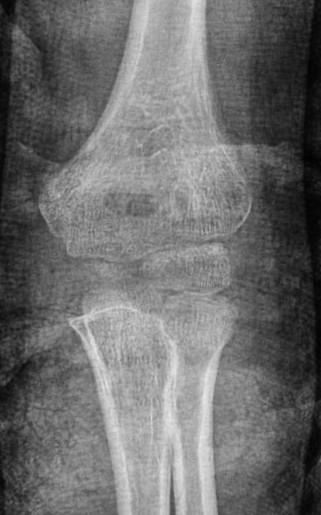

Case 2. Chronic Monteggia with deformed radial head